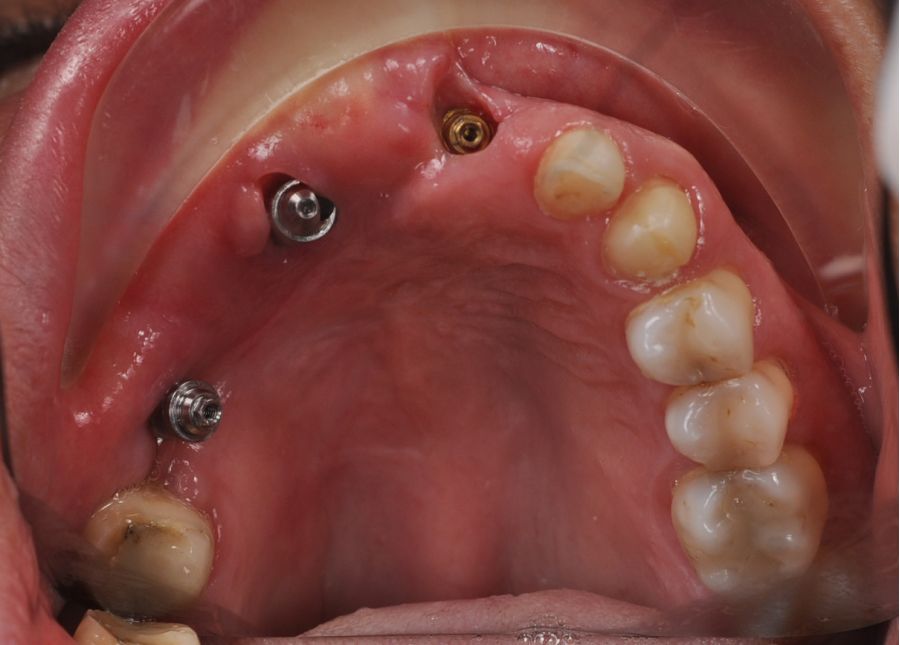

Una vez finalizada la radioterapia, la paciente se encontraba libre de enfermedad. Por lo que se procedió a la restauración definitiva implantosoportada. Tras la segunda fase, se colocaron dos pilares transepiteliales Multiunit Ò rectos y un pilar Multunit Ò angulado de 17º (Figura 10).

Para la fabricación de las estructuras, se eligió el óxido de zirconio monolítico como material restaurador sobre interfases metálicas en el puente implantosoportado, y coronas de óxido de zirconio monolítico en los dientes tallados previamente (1.7, 1.6, 2.2 y 2.3). Se tomaron impresiones de cubeta abierta con silicona de adición pesada y fluida (Zhermack Elite HD, Gmbh). Se realizó una prueba de pasividad analógica y el resto del proceso se confeccionó de manera digital, por lo que se hicieron pruebas estéticas de dientes impresas en 3D sobre interfases metálicas, para hacer todos los ajustes de función y estética previos al fresado del zirconio monolítico (Figuras 11, 12 y 13).